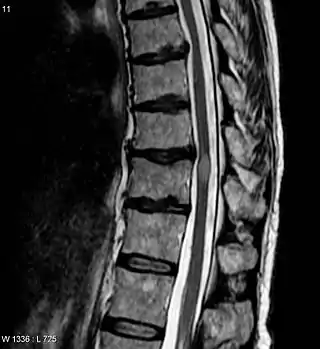

![]() Imagen de resonancia magnética que muestra una lesión de mielitis transversa (ligeramente a la derecha, de forma oval y color más claro). La paciente se recuperó tres meses después. | ||

El diagnóstico se hace a través de la historia clínica, el examen físico, el estudio del líquido cefalorraquídeo (punción lumbar) y, en algunos casos, la resonancia magnética de la médula espinal.